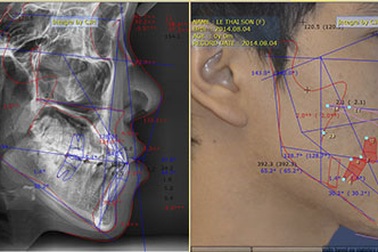

Cơ hội niềng răng miễn phí 100%Tham gia vào chương trình vòng quay may mắn do Bệnh viện Răng Hàm Mặt Sài Gòn tổ chức, bạn có cơ hội là 1 trong 20 người được điều trị nha khoa với giá 0 đồng.